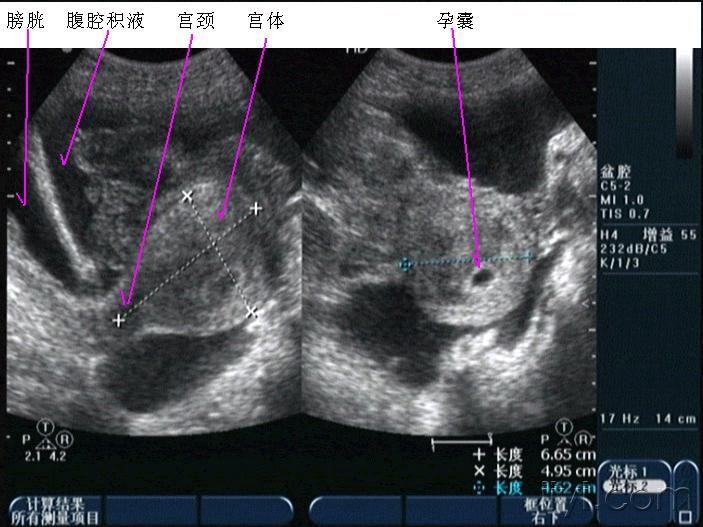

早孕并黄体破裂

晚上房事后腹痛入院,第二天早晨8点多超声所见如下,手术证术为黄体破裂。